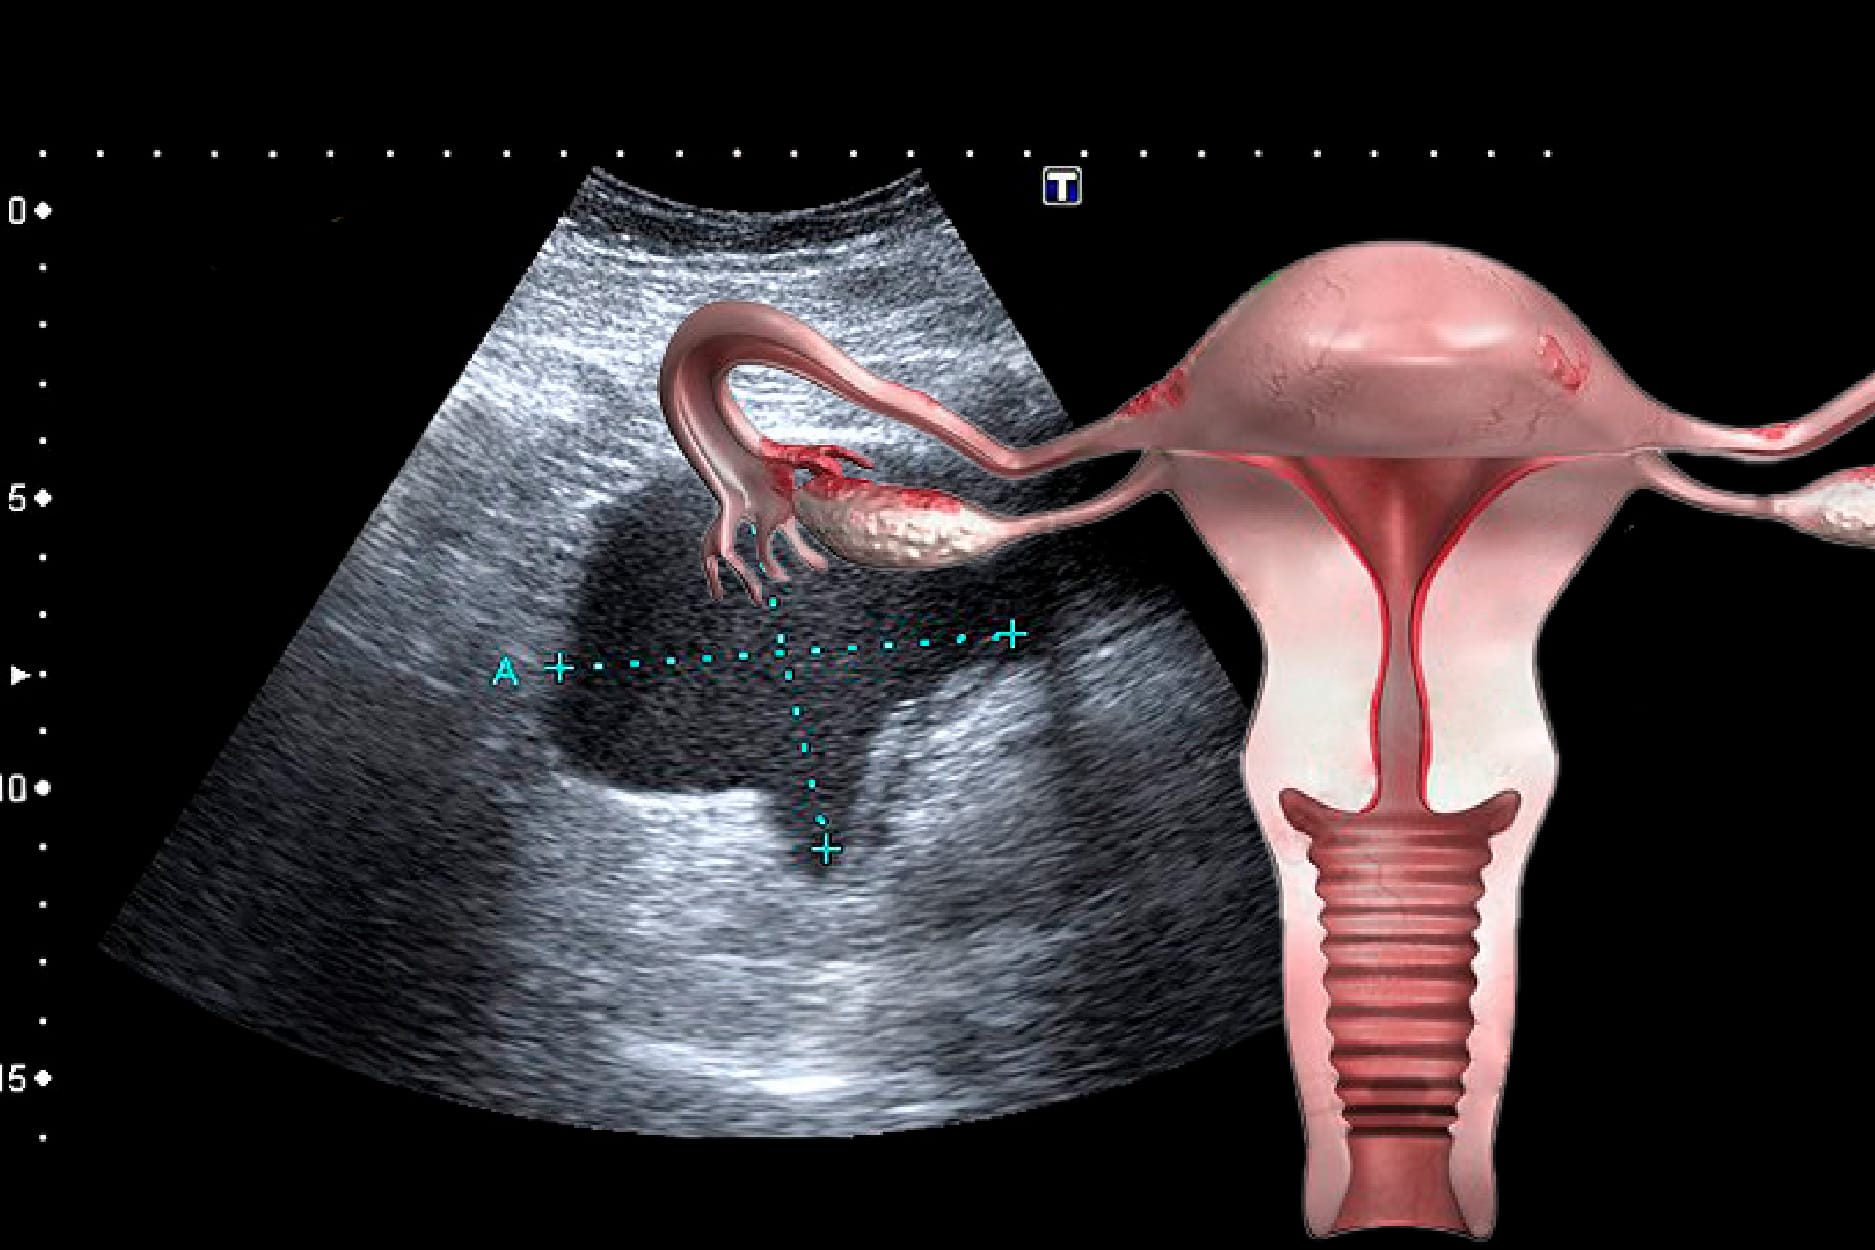

O pólipo endometrial também pode ser assintomático e regredir espontaneamente em até 30% dos casos, principalmente quando únicos e menores de 1 cm. Sem dúvida a ultrassonografia transvaginal auxiliará no diagnóstico e no acompanhamento (na fotografia abaixo e à esquerda, o pólipo endometrial está identificado pela imagem típica do vaso sanguíneo que o alimenta).